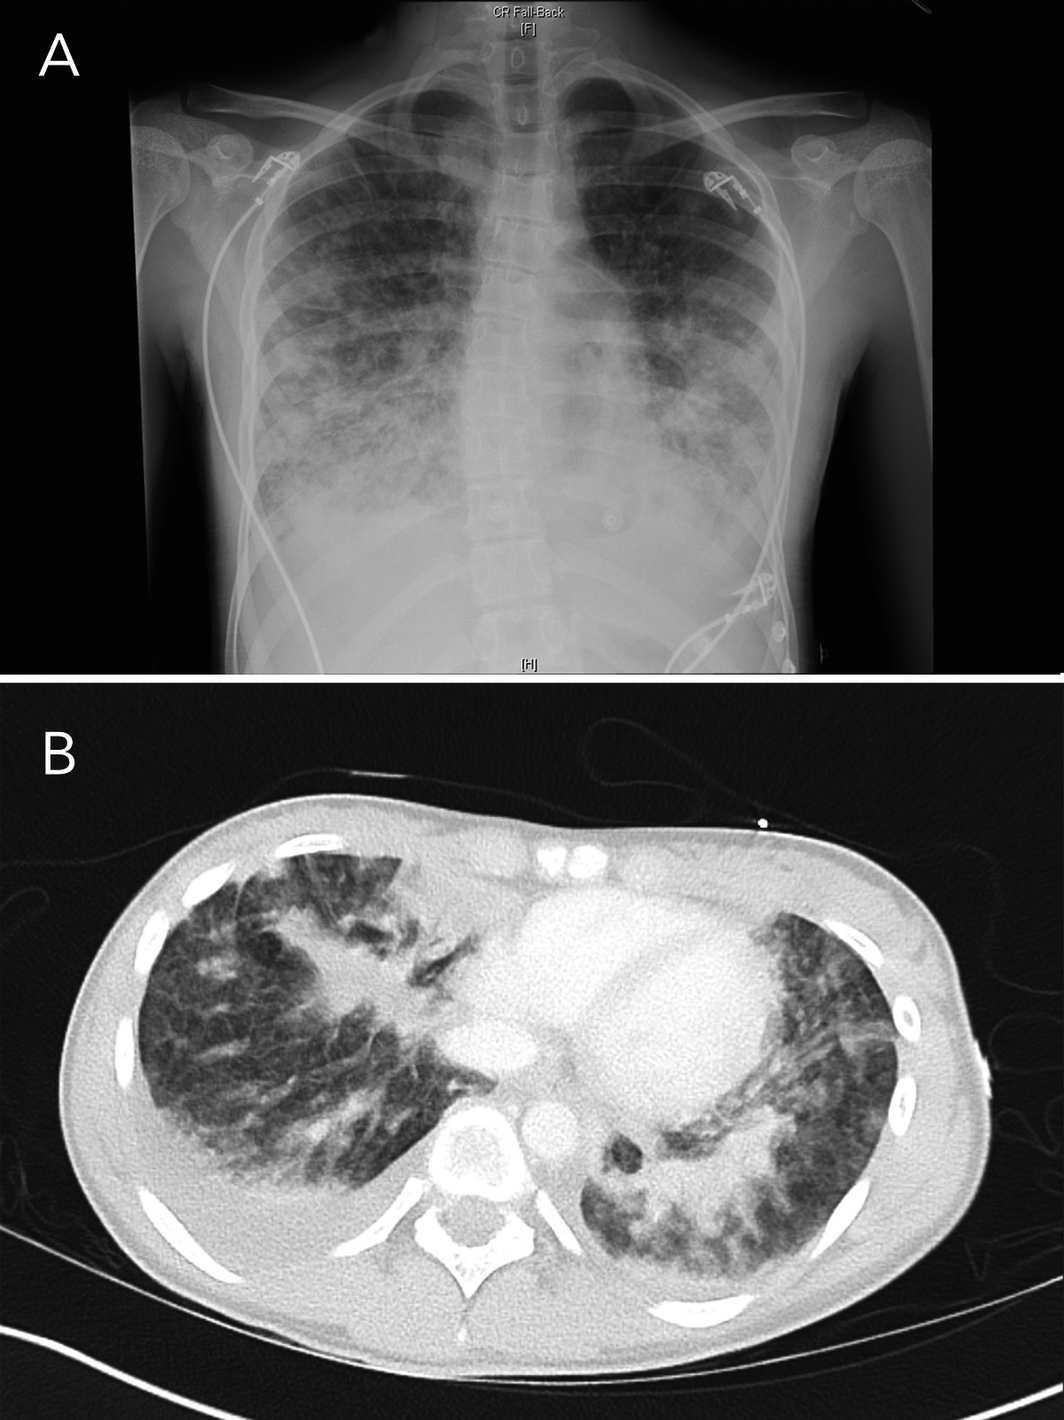

In September 2020, a Sydney public health unit was notified of the admission to a tertiary paediatric hospital intensive care unit of a 15‐year‐old girl with suspected e‐cigarette or vaping product use‐associated lung injury (EVALI), a pulmonary syndrome first reported in the United States.1 The girl had presented to another Sydney hospital with a 4‐day history of dysuria, urinary frequency and back pain followed by 2 days of vomiting and rigors. She was initially treated for urosepsis with intravenous antibiotics. She reported vaping nicotine two to three times weekly for the previous 7 months. She was febrile at 38°C, with a heart rate of 120–140 beats per minute, blood pressure of 110/80 mmHg, respiratory rate of 20 breaths per minute, and oxygen saturation of 92–95% on room air. A chest x‐ray showed bilateral pulmonary infiltrates that were worse in the lower zones (Box 1). Within hours, she became hypoxic, with oxygen saturation of 87% on room air. Abdominal computed tomography showed no abdominal pathology, but there were extensive pulmonary infiltrates in the lung bases with bilateral effusions (Box 1). Her urine drug screen result on the day of admission was positive for cannabinoids and benzodiazepines.

In summary, our patient had a similar presentation to other reported EVALI cases and fulfilled the Centers for Disease Control and Prevention case definition of EVALI as she used e‐cigarettes within 90 days of her symptom onset, had bilateral pulmonary infiltrates on chest x‐ray and computed tomography, and there was absence of pulmonary infection.1,2

Box 1 – Chest x‐ray (A) and base of lung computed tomography (B) on first day of hospital admission, showing increased insterstitial opacities bilaterally, with areas of airspace opacities in the lower zones